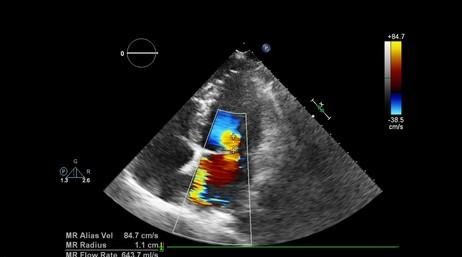

If that sounds familiar, mitral valve stenosis might be the culprit. It’s a condition where your heart’s mitral valve narrows, making it harder for blood to flow between two of its most important chambers. And yes, it can sneak up on you.

Think of your mitral valve like a door that’s supposed to swing open easily to let blood through. In mitral valve stenosis, that door becomes stiff, narrow, or even sticky—causing blood to get bottlenecked. That puts strain on your heart, and over time, it can affect your lungs, rhythm, and energy levels too.

A narrowing of the mitral valve that restricts blood flow between the left atrium and ventricle.